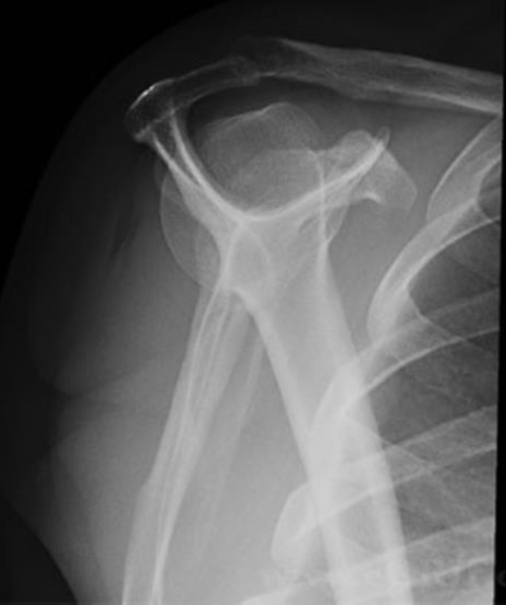

What is this view of the shoulder? what views are missing?

Scapular Y Shoulder

MISSING:

AP

AP internal rotation

AP external rotation

Axial

AC Joints (spot, weighted